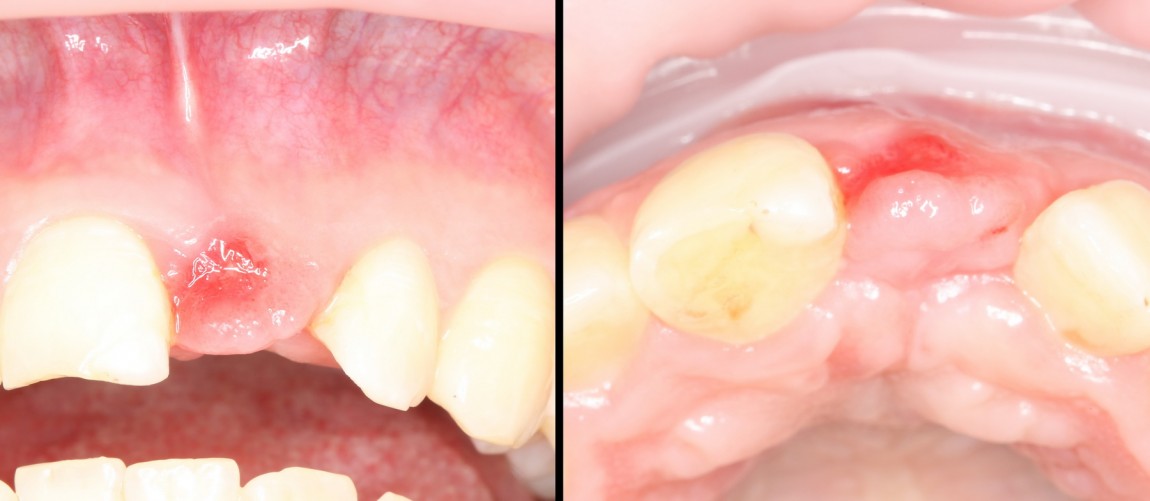

Через год после травмы, девушка обратилась в нашу клинику для восстановления отсутствующего зуба. К тому моменту у нее уже был временный съемный протез, изготовленный в вышеозначенном стоматологическом кабинете, ну и, вот какая клиническая картина:

Хочу спросить вас, уважаемые друзья, можно ли в таком состоянии и при таких объемах альвеолярного гребня поставить имплантат в область отсутствующего зуба? Безусловно, можно. Для этого нужно просто взять имплантат потоньше и поставить его подальше, в сторону неба — и он нормально интегрируется.

Возможно ли получить на подобном импланте более-менее приемлемый эстетический и функциональный результат? Вряд ли. Если за пределами эстетически значимой зоны мы можем пойти на эстетические компромиссы (все равно никто не увидит), то проблемы с эстетикой в области передней группы зубов… да еще у девушки…. так можно человеку всю личную жизнь испортить.

Поэтому, несмотря на возможность установить имплантат потоньше и подальше, мы планируем в ходе имплантологического лечения увеличение объема альвеолярного гребня до приемлемого уровня с помощью остеопластических процедур. Ориентиром «приемлемого уровня» является симметричный центральный резец. В идеале, вокруг нашего импланта должен быть абсолютно такой же объем тканей — только так мы можем добиться эстетического результат лечения.